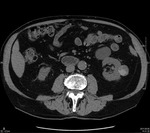

W związku z podejrzeniem występowania rozrostu w obrębie torbieli nerki u chorego w trybie ambulatoryjnym wykonano wielofazowe badanie metodą tomografii komputerowej (TK) jamy brzusznej (faza przeglądowa, faza tętnicza, korowo-rdzeniowa 30-50 s po dożylnym podaniu środka cieniującego i późna faza pokontrastowa, faza wydzielnicza, ok. 3-5 min po podaniu środka cieniującego).1 W badaniu potwierdzono występowanie w obu nerkach kilku zmian o cechach torbieli, zaś w obrębie nerki lewej torbieli z położonym obwodowo obszarem wzmocnienia pokontrastowego (ryc. 2A-D).